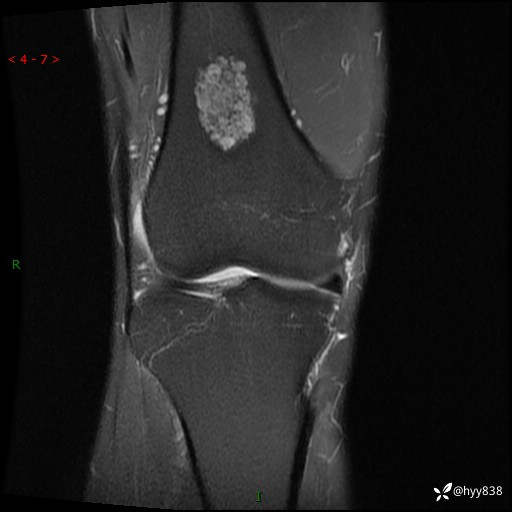

MRI

img

内生软骨瘤 (27)